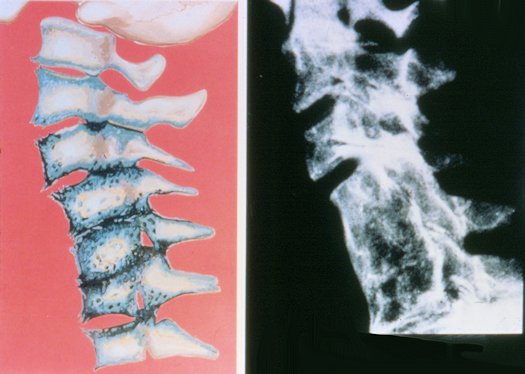

3) If left to continue, the degeneration progresses; bone spurs form along the margins of the bones. Joint surfaces become rough and irregular. Discs in the neck begin to narrow and show signs of collapse. These are signs of progressive degeneration.

4) Now you can see a great deal of decay is present. There are many sharp bone spurs and the soft tissues begin to decay. Fusion has begun which causes the bones to become irregular blocks of calcium. Nerve roots are being destroyed. This stage is very difficult to treat.

5) As if things couldn’t get worse, the extreme stage of arthritis.